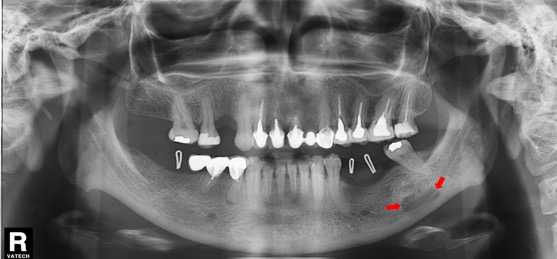

Paciente femenino de 51 años de edad, quien acudió a la consulta para evaluación del reborde alveolar previo a la colocación de implantes dentales. A la evaluación de la radiografía panorámica (Figura 3) se evidenció una imagen radiolúcida de límites definidos, bordes corticalizados, de forma ovoide, localizada en el cuerpo mandibular izquierdo, proxima a la basal mandibular, y proyectada sobre el canal mandibular. En el estudio por TCHC se observó en los cortes coronal y axial, una concavidad bien delimitada, formada a expensas de la tabla ósea lingual (Figura 4a-b). En el corte sagital (Figura 4c) y reconstrucciones 3D (Figura 4d-e) se evidenció la imagen hipodensa bien delimitada en la región antegonial, sin compromiso de la base de la mandíbula o el canal mandibular. La imagen muestró signos tomográficos compatibles con COS Tipo I.

Figura 4 FIGURA 4. Reconstrucciones multiplanares de Tomografía Computarizada de Haz cónico donde se observa en a, b y c, vistas coronal, axial y sagital respectivamente, en el lado izquierdo una imagen hipodensa, ovoide ubicada en proximidad al canal mandibular,cuya concavidad es dependiente de la tabla ósea lingual (Flechas rojas). En la reconstrucción volumétrica en vista lateral interna (d) e infero-superior (e), se observa la concavidad a expensas de la tabla lingual, la relación con el canal mandibular y el adelgazamiento de la base de la mandíbula.